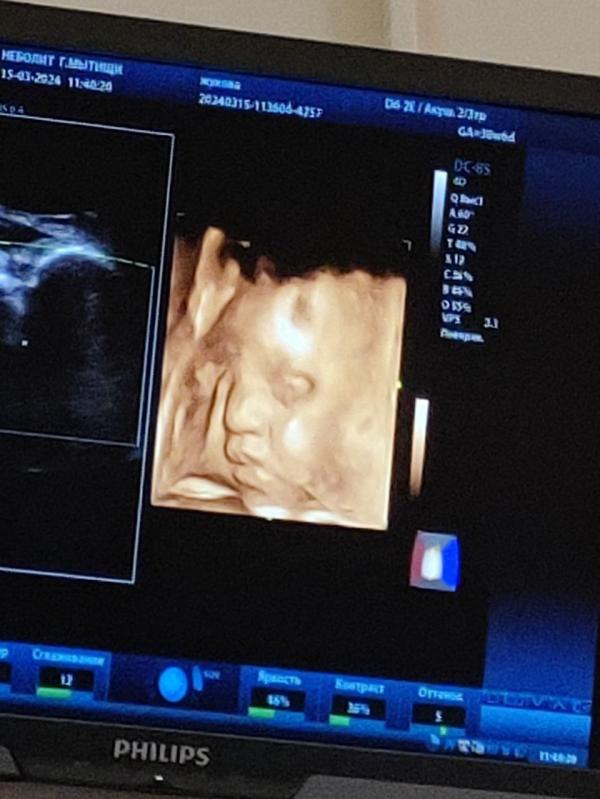

И вот наша дамочка с таким выдающимся носом, все его отметили) шуточки льются от всех рекой😂

- что с таким носом только кесарево назначат 😂

- что толкает меня не локтями, а носом ковыряет

Хорошенький носик 🩷